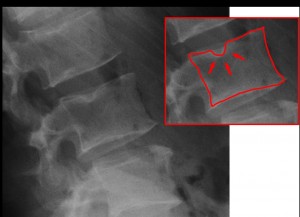

Ce n’est que récemment qu’il a été envisagé que les malformations des disques herniaires pouvaient être induites par le modelé de la surface des plateaux vertébraux sur lesquels ils reposent. L’autopsie de cadavres a montré que les sujets dont les assises vertébrales étaient concaves ne présentaient aucune anomalie, alors que ceux chez qui elles étaient planes avaient développé des hernies discales. Dans ce cas, le cartilage intervertébral développe des boursouflures dénommées nodules de Schmorl du nom du premier descripteur, un pathologiste allemand du siècle dernier : le cartilage du disque pénètre l’os spongieux du corps vertébral. L’effet de ces nodules est bien visible en radiographie car ils provoquent des encoches dans le corps vertébral.

Les techniques de morphométrie géométrique utilisées font appel à des analyses canoniques des variables linéaires mesurées sur les corps vertébraux de la dernière vertèbre thoracique (T12) et de la première lombaire (L1) comme illustré sur la figure suivante.

C’est en effet au niveau de leur contact que les douleurs irradient pour cause de malfaçon : les nodules de Schmorl, hernies entre disques vertébraux étant la principale cause du mal de dos.